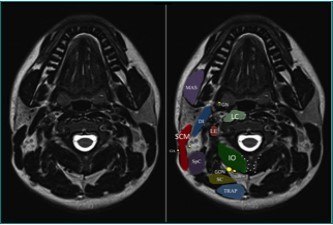

The largest of the three occipital nerves, the GON, arises from the dorsal root ganglion (DRG) of C2, running inferiorly between the arch of C1 (atlas) and the lamina of C2 (axis), lateral to the lateral atlanto-axial (AA) joint and deep to the inferior oblique capitus (IOC) muscle. The GON then curves medially and cephalad over the IOC Figure 1. As the GON travels cephalad up the neck, it travels over the posterior surface of the IOC to pierce the semispinalis capitis muscle, deep to the trapezius muscle, Figure 2 onto the posterior skull through a muscular sling formed by the aponeurosis of the sternocleidomastoid muscle (SCM) and the trapezius muscle at the skull attachment (the conjoined tendon) Figure 3. where it is joined laterally by the occipital artery. The GON can be found at this point lying in a palpable groove, immediately medial to the occipital artery and lateral to occipital prominence (the inion) Figure 1. There are several areas of potential entrapment of the GON

Figure 1.MRI anatomy of the upper cervical region. DI = digastric muscle; IO = inferior oblique muscle; LC = longus colli muscle; LE = levator scapulae muscle; MAS = masseter muscle; SC = semispinalis cervicis muscle; SCM = sternocleidomastoid muscle; SpC = splenius capitis muscle; TRAP = trapezius muscle; GA = great auricular nerve; GON = greater occipital nerve; GN = glossopharygeal nerve. LON = lesser occipital nerve; TON = third occipital nerve. Note the bifid spinous process of C2. (Image courtesy of Andrea Trescot, MD Clinical presentation